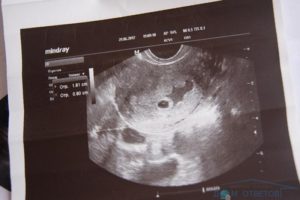

Плановое ультразвуковое исследование, которое женщина проходит в первый период беременности, способно выявить отслойку до первых ее симптомных проявлений.

На УЗИ сразу станет понятно наличие у вас этой патологии, а при обнаружения можно точно определить ее вид (частичная или полная).

Прежде всего, вас должен осмотреть гинеколог и с помощью ультразвука определить состояние хориона, а также наличие гематомы.

Врач прослушает сердцебиение ребёнка (это можно осуществить только по истечении шестой недели беременности, а обнаружить плод – на третьей или четвёртой неделе).

При неполной отслойке плодного яйца на УЗИ можно увидеть гематому – кровоподтек на месте поврежденных сосудов ворсин хориона. В случае значительной площади отслойки данную патологию можно увидеть при УЗИ обследовании. При влагалищном обследовании шейка матки закрыта, либо чуть приоткрыта, величина матки соответствует гестационной неделе.

Полная отслойка плодного яйца – это состояние, при котором зародыш с оболочками никак не соединен с маткой и находится в ее полости, что можно увидеть на УЗИ. На ультразвуковом обследовании также обнаруживается гематома. При влагалищном обследовании шейка матки раскрыта и размягчена. Размеры матки либо соответствуют сроку беременности, либо уменьшены.